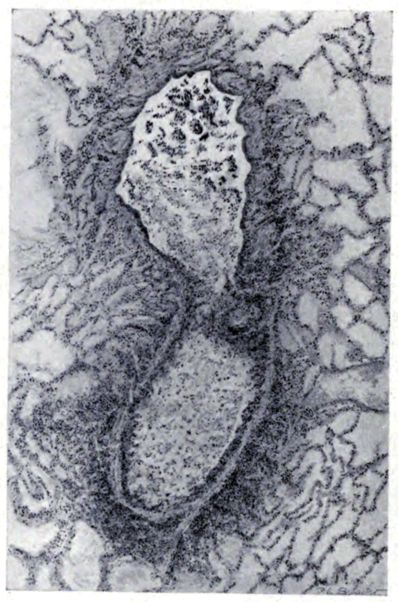

A more striking picture, however, even than this aplastic alveolar exudate appears in the terminal bronchioles. In many instances, these are conspicuous on account of their size, for they are dilated to form prominent, often irregular, sacs (Fig. XV). The distention of these terminal bronchioles may be so great that the surrounding alveoli are compressed. What makes them even more conspicuous is their lining, once epithelium, but now a swollen, thick, homogeneously staining material, with complete loss of architecture; the material forms (with hematoxylin and eosin) a red band limiting the lung tissue and sharply demarcating it from the exudate within the bronchioles (48, 92). However, this ribbon of red, often thickened by fibrin deposition, is not always pure, for bacteria thrive in the dead tissue. They occur singly, paired, in chains, and also as circumscribed, dense masses which in size and position, simulate nuclei (162) (Fig. XVI). This same hyalinization of the epithelium, it will be recalled, occurs in the larger bronchi (Fig. V), and there, too, bacteria frequently develop in the dead tissue (Fig. VIII). In the smallest bronchiolar ramifications, acute epithelial necrosis is not infrequently encountered, even when the surrounding lung tissue is relatively normal (Fig. XVI). That the process does not stop with the epithelium, but, as in the larger bronchi, may extend through the entire structure of the bronchioles, is manifest. Even the alveolar walls may be involved and frequently homogeneous pink or red bands, now the phantom of the former viable lung tissue, mark the presence of the old wall of the alveolus (Fig. XVII). Occasionally, some architecture remains in this pink ribbon and then the involvement seems to be primarily in the vessels of the wall. Not all the vessels are involved, and next to a hyaline thrombus in one, there may be fresh blood, usually red blood, in its neighbor. The alveolar epithelium is usually denuded and thus accentuates the intensity of the change.

The acute death which involves the tracheal, bronchial, and bronchiolar epithelium and which may extend beyond the epithelium into the walls of these structures and kill en masse the walls of the alveoli, is a lesion which does not occur in other types of acute pulmonary infection. However, in influenza, as after exposure to pulmonary irritating gases, it is the lesion of characterization (158,159). The effects of this change, of course, where it involves 22the alveolar wall, will vary with the extent of the process; but given an absolutely necrotic wall, as yet unstrengthened by inflammatory reaction, an expected result would be its rupture with respiratory movement. The point of rupture is important, but where so many alveoli are involved, disturbance of continuity will occur, occasionally in such position that the result will be the escape of air into the interstitial tissues.[7] There is ample evidence that this happens. Indeed, among the clinical manifestations of the disease, interstitial emphysema of the lung spreading through the fascial planes to the subcutaneous tissues of neck and thorax is well known; the phenomenon is more frequent and extensive in influenza than in any other disease (8, 17, 52, 143).